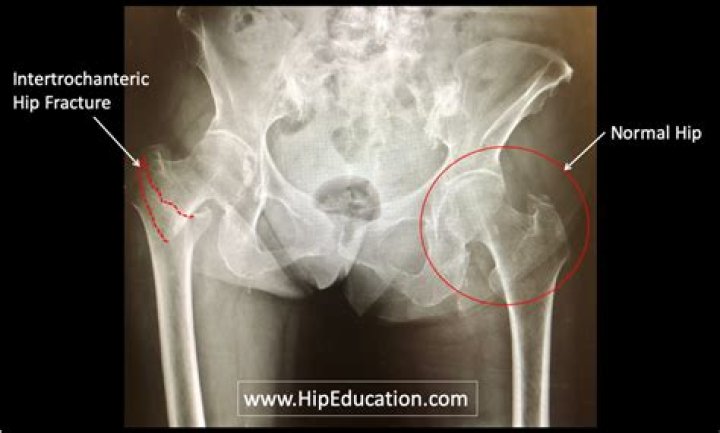

Why do elderly break their hips?

Hip fracture is more common in older people. This is because bones become thinner and weaker from calcium loss as a person ages. This is generally due to osteoporosis. Bones affected by osteoporosis are more likely to break if you fall.

Can an elderly person break a hip without falling?

But if you have very thin bones from osteoporosis or another problem, you could break your hip without falling. In rare cases, people have only thigh or knee pain. They may be able to walk.